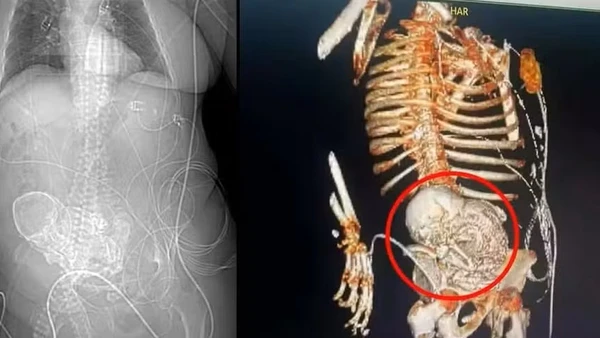

Uma idosa colombiana de 82 anos descobriu que enfrentava uma condição médica raríssima. Com fortes queixas de dor de barriga, a idosa procurou o Hospital de Bogotá e os exames de imagem revelaram algo que pode parecer inacreditável, chocando o público na época: ela carregava um feto já calcificado há mais de 40 anos. A síndrome é chamada de litopedia ou "bebê de pedra".

A calcificação de um feto dentro do corpo ocorre quando a gravidez é ectópica - o feto se desenvolve fora do útero - e não é diagnosticada nem o bebê expelido. Ao longo dos anos, o organismo cria uma camada de cálcio ao redor dele, como uma forma de proteção, transformando o feto já morto em um material endurecido que, em casos raros, pode permanecer silenciosamente dentro do corpo.

Litopedia ou bebê de pedra por Reprodução

No caso da idosa descoberto em 2013, o feto pesava cerca de 1,8 quilos, mas mesmo assim permaneceu anos em seu abdômen sem que ela percebesse nada. Na maioria das vezes, os sintomas só aparecem quando a calcificação pressiona órgãos internos, como aconteceu com a mulher colombiana.

Raríssima, a litopedia possui menos de 300 casos documentados em toda a história da medicina e acomete cerca de 1 a cada 11 mil gestações.